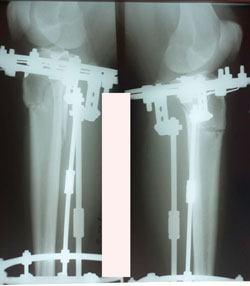

на фиксации

image-08-04-21-12-44-3.jpg

image-08-04-21-12-44-1.jpg

image-08-04-21-12-44.jpg